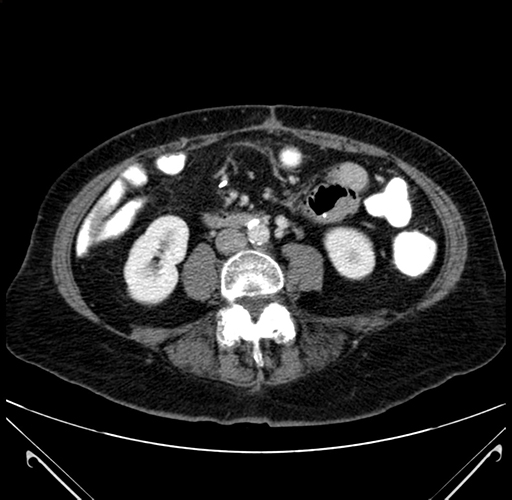

Axial Venous